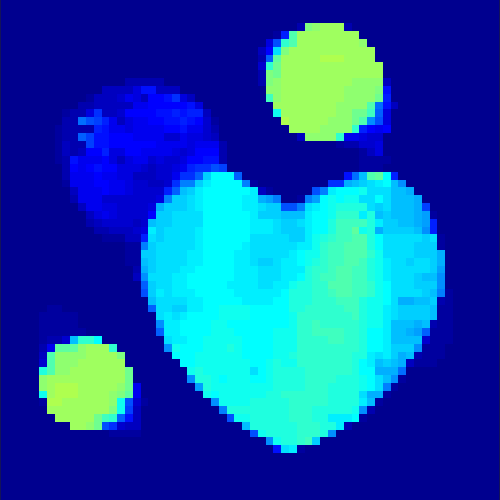

The first data set consists of a heart-shaped region and three circles on a static background (see figure 1 (a)). The two smaller circles are assumed to belong to

the same tissue type and therefore to the same subregion, which causes a total of four subregions, including the background. To simulate a more realistic application of dynamic SPECT

imaging, we used a synthesized representation of a rat liver as a second data set (see figure 1 (b)). The temporal concentration curves used to simulate the data sets

are shown in figure 2. As before, the total number of subregions was chosen to be equal to four in order to provide a both simple and realistic shape model.

In a first test, every image sequence was reconstructed out of the exact given sinograms. Additionally we tested noise corrupted data by first scaling the sinogram by a parameter , corrupting them with Poisson noise via the MATLAB imaging toolbox command imnoise and finally rescaling the image to the original range (see figure 4). The average count number per time step (i.e. the average of the discrete -norm of the data at each time step) is approximately in case of the heart-shaped data set and ca. in case of the rat liver simulation. The results at a certain number of time steps can be seen in figure 6 and 7. For comparison, we additionally performed a reconstruction with a simple alternating EM method, keeping the assumption that the tracer can be modelled as a sum of indicator functions and subconcentration curves, but neglecting any regularization terms. In all tests, the outer iteration number was set to 1000 with 10000 inner iterations per subproblem, to obtain a result within a reasonable time period. As stopping criterion, we chose the primal dual residual (cp. [12]) for the inner and the maximum over the Frobenius norms of and for the outer iterations. The results are displayed in 6 and 7 respectively.

As one can see in both figures, the reconstruction method applied to each data set performs very well, especially in contrast to the simple alternating EM method. This clearly shows the benefits of the proposed regularization methods. In case of noise-free given data, the shape of every object, where especially the heart is of higher interest, is clearly defined. As expected, we often observe errors in the edges of each region and where two regions are directly connected (the heart and the upper left circle). This causes the algorithm to incorrectly assign these pixels to another region. Furthermore, the reconstruction difficulties increase with an increase in noise. Some more pixels are assigned to the wrong region, which leads to a small hole-like structure within the heart region and causes a slight blurring effect. In the second data set the method clearly outperforms several other approaches by providing very clearly defined regions and even reconstructing fine structures of the phantom. However, as mentioned before, a clear reconstruction of the rat liver required highly optimized parameter sets, which makes the whole problem quite susceptible to parameter changes.